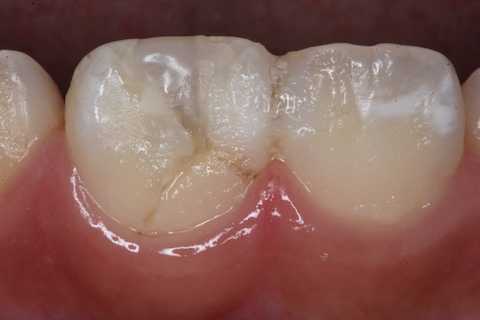

リクエストがあったが、業務経験の長い歯科医師でないと解りにくいのではないかと思う。というか、歯科医師でも何が起こっているのか意味不明だと思う。80代男性、左上7、歯髄壊死>Per(根尖性歯周炎:歯髄が壊死して炎症が歯根外に波及している状態)多分CRの辺縁封鎖が破れて歯髄に細菌感染したものと思われる。2週間程前から痛かったそうだ。やっと昨日位から痛みが治まった。歯髄があらかた死ぬまでが痛い。ズキズキの激痛だ。よく我慢しましたね。受付が杓子定規だから今日しか空いていないとか言ったのだろう。僕に直電すればのたうちまわらすによかったと思うのだが。近心根付近の根尖相当部が腫れている。歯ぎしりが酷い方だ。歯のすり減り具合でわかると思う。内部の歯質にもCR部分にもクラックが多数見える。ここから細菌感染したのだろう。冠部歯髄は壊死していて空洞になっている。口蓋根は2次象牙質で塞がれているらしく探せない。頬側の2根には超音波スケーラーのエンドチップが入る。頬側近心根の歯髄は完全に壊死していたが、頬側遠心根は完全に壊死してはおらず、痛みを感じ、出血する。少し赤いので分かると思う。α-TCPの2回法で根管充填したが、1回目で出血した血液がセメントに混ざっているのが見えると思う。2回目で内部を固めてCR充填して終わった。こんな感じで1回で処置は終わる。従来法しか知らない歯科医師は驚くと思う。えっ、こんなことで治るの?!